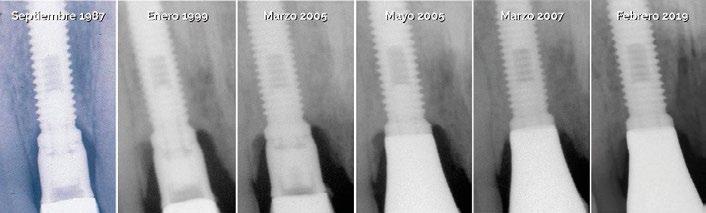

Durante los 17 años siguientes, ambos implantes funcionaron de manera satisfactoria, cumpliendo correctamente su cometido tanto en el plano funcional como en el estético. Sin embargo, en 2005 fue necesario sustituir la corona del incisivo central debido a una nueva fractura. Para ello se recurrió a la tecnología disponible en ese momento: se diseñó un pilar en resina acrílica, que posteriormente fue escaneado y fresado en zirconio (Procera), sobre el cual se confeccionó una corona totalmente cerámica en alúmina. (Fig. 9 y 10)

Dos años después de la colocación de esta nueva restauración, observamos que el nivel óseo, que se había mantenido estable durante 17 años, mostraba una mejora notable tras la colocación del nuevo pilar y la nueva corona. Este cambio se aprecia claramente al comparar las radiografías de 2005 con 2007, situación que se ha mantenido hasta la actualidad. (Fig. 11) Es muy probable que el cambio óseo observado se deba a que, para la nueva restauración, se utilizó un pilar mecanizado mediante

maquinaria de precisión en zirconio (Procera), lo que permitió reducir significativamente el espacio en la interfase pilar-implante (gap). Asimismo, no es descartable que a este cambio también haya contribuido la disminución de los micromovimientos del pilar sobre la cabeza del implante, al haberse utilizado un tornillo TorqTiite (Nobel Biocare) ajustado con llave dinamométrica a 35 Ncm, en lugar de hacerlo manualmente a 10–15 Ncm, como se había realizado con el pilar original de Jemt.